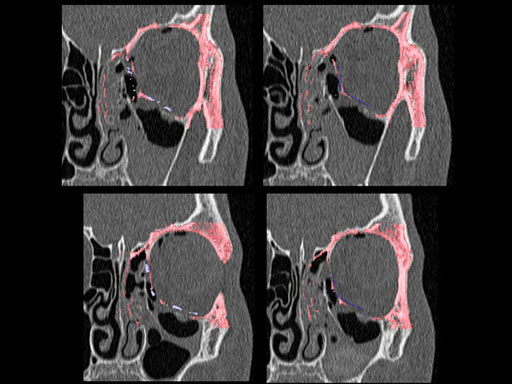

Furthermore, as orbital floor fractures are quite frequently associated with medial wall fractures; anatomic restoration especially in the transition zone between both wall is a demanding procedure. As described by B. Hammer, the orbital floor has an initial shallow convex section behind the rim, then inclines upward behind the globe, and inclines upward to meet the medial wall, creating a distinct bulge behind the globe. These convex curves of the medial wall and floor create a postbulbar constriction of the orbital cavity, which must be reconstructed when the orbit is rebuilt following fractures. Treatment is directed at precise anatomical reconstruction of orbital shape and volume in order to restore the correct position of the eye. To provide surgeons with an adequate implant that addresses the requirements of two wall acute orbital fractures or for secondary reconstruction of enophthalmos and dystopia, a new series of preformed orbital plates was developed for the new orbital matrix system.

Unlike the existing two-dimensional mesh implants, the geometry of the new preformed plates will be adequate to match the individual anatomic situation of the patient in almost any case. However, the mesh parts can be individually adjusted if necessary. In these cases the solid part in the central posterior area needs to remain untouched. Areas of the orbit that do not require a bridging can be spared out by trimming the implant along the designated cutting lines in the height of the medial wall and/or length of the orbital floor area. The lateral anterior part of the plate is intentionally pre-bent higher than the orbital rim anatomy to allow free plate movement during plate positioning.

The Preformed Orbital Plates are indicated for trauma repair and reconstruction of fractures of the orbital floor, medial orbital wall or combined fractures of floor and medial wall. It should be noted that in three-wall fractures where the lateral wall is also involved, a second orbital implant, ( i. e. the mesh plate) must be used in addition to the pre-formed orbital plate.

30 year old male patient with fracture of left orbital floor and medial wall.

Provided by Dr Dr Marc C Metzger, Freiburg, Germany.